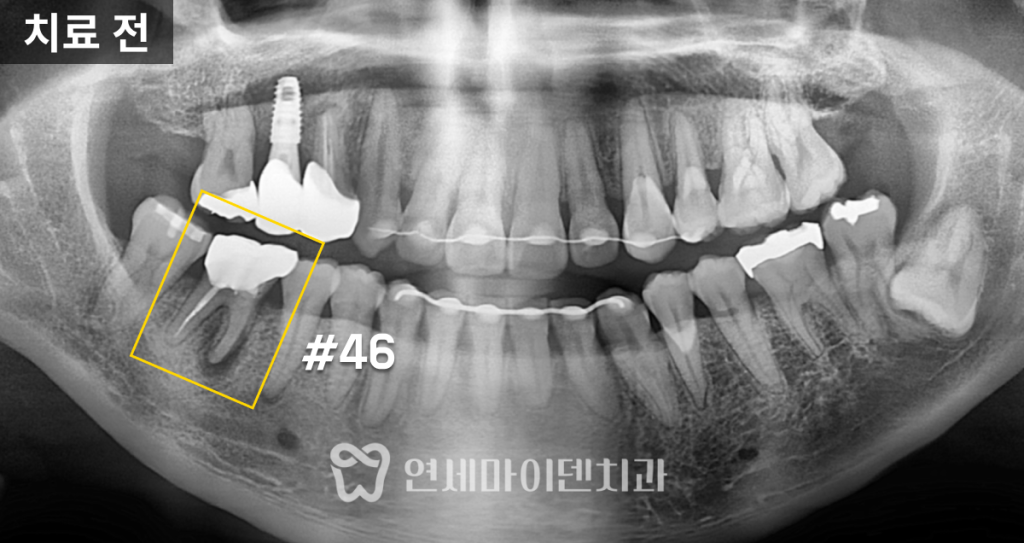

반대편 어금니(#46)는

스플린트 크라운으로 수복되어 있었습니다.겉으로 보기엔 멀쩡했지만,

내부에는 깊은 충치가 진행돼 있었습니다.보철물을 제거하자 치아 내부 조직이 심하게 손상되어 있었고,

결국 보존 불가로 판단했습니다.

이에 따라 발치 후 즉시 임플란트를 진행했습니다.

다행히 치조골 상태가 양호해 즉시 식립이 가능했습니다.

임플란트 식립 후 골이식과 멤브레인 적용을 통해 뼈의 안정화를 유도했고,

2주 뒤 봉합사 제거 후 출국하실 수 있도록 계획했습니다.최종 보철물은 귀국 시기에 맞춰 맞춤 제작하여 완성했습니다.